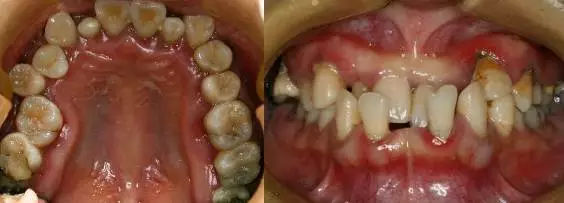

1、影响口腔健康

牙列拥挤不齐使牙齿不能自洁,菌斑结石堆积,引起龋病及牙龈牙周的炎症;同时牙齿的错位、咬合异常也可造成牙周损害;牙列稀疏则容易发生食物嵌塞而伤害牙龈牙周的健康。